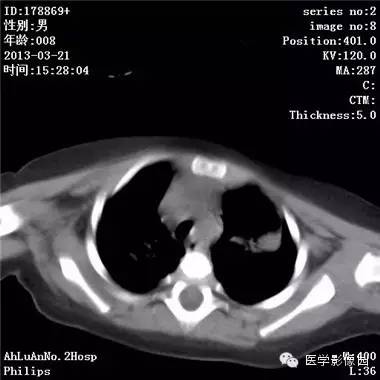

【病例】支气管异物1例CT影像表现

患儿男,8个月,呛咳,发热一周。实验室检查白细胞及中性粒细胞增高。

两肺肺纹理增多、增粗,右肺可见斑片状、片絮状模糊影,边界欠清;左肺上叶见楔形高密度影,内可见支气管征,尖端指向肺门;左肺下叶肺野透亮度增强;另见左肺主支气管内可见块状软组织密度影。

支气管异物(花生米)伴两肺炎症(追问病史,患儿奶奶层于一周前喂食患儿花生米,当时疑似“呛进去”,后来见好了也就没留意)。